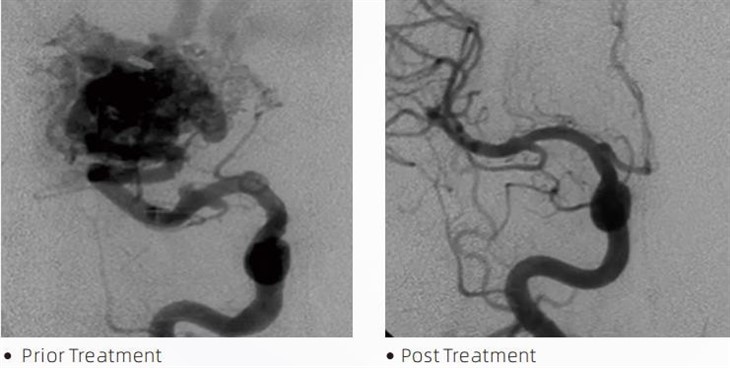

LafaTMMae glud embolig yn ddyfais feddygol a ddefnyddir gan niwroradiolegwyr ymyriadol yn ystod gweithdrefnau lleiaf ymledol i drin cyflyrau fel ymlediadau yr ymennydd, camffurfiadau arteriovenous a thiwmorau. Mae glud embolig Lafa yn cynnig buddion lluosog i weithwyr meddygol proffesiynol a chleifion fel ei gilydd o ran diogelwch, rhwyddineb defnydd ac effeithiolrwydd. Mae lafa yn gallu selio pibellau gwaed yn gyflym ac yn effeithlon. Mae'r broses yn cynnwys chwistrellu'r glud yn uniongyrchol i'r llong a dargedir, lle mae'n polymeru ac yn caledu i mewn i fàs tebyg i gast sy'n llenwi'r aniwrysm neu gamffurfiad. Yna mae'n torri'r llif gwaed i'r briw i bob pwrpas, gan ei atal rhag rhwygo a lleihau'r risg o niwed parhaol neu strôc. Mae lafa yn cynnwys Lafa-12, Lafa-18 a Lafa-34. Mae pob fformiwleiddiad wedi'i gynllunio i ddiwallu anghenion clinigol penodol. Mae lafa-18 yn fformiwleiddiad safonol at ddefnydd cyffredinol. Mae lafa-34 yn glud gludedd uchel ar gyfer llestri llif uchel. Er bod gan Lafa-12 gludedd is ac mae'n haws ei lifo, gan ganiatáu ar gyfer micro-batiau o'r neilltu. Gyda'r opsiynau hyn, gall niwroradiolegwyr ymyriadol ddewis y fformwleiddiadau Lafa addas i sicrhau'r canlyniadau gorau posibl. Un o nodweddion mwyaf rhyfeddol Lafa yw ei briodweddau nad yw'n gludiog. Mae'r sylwedd hwn wedi'i lunio'n arbennig i aros yn sefydlog nes iddo gyrraedd yr ardal darged. Mae'r nodwedd hon yn golygu y gellir gosod glud embolig Lafa yn gywir o fewn y rhydweli ac aros yno heb lynu na bondio i'r meinwe amgylchynol.